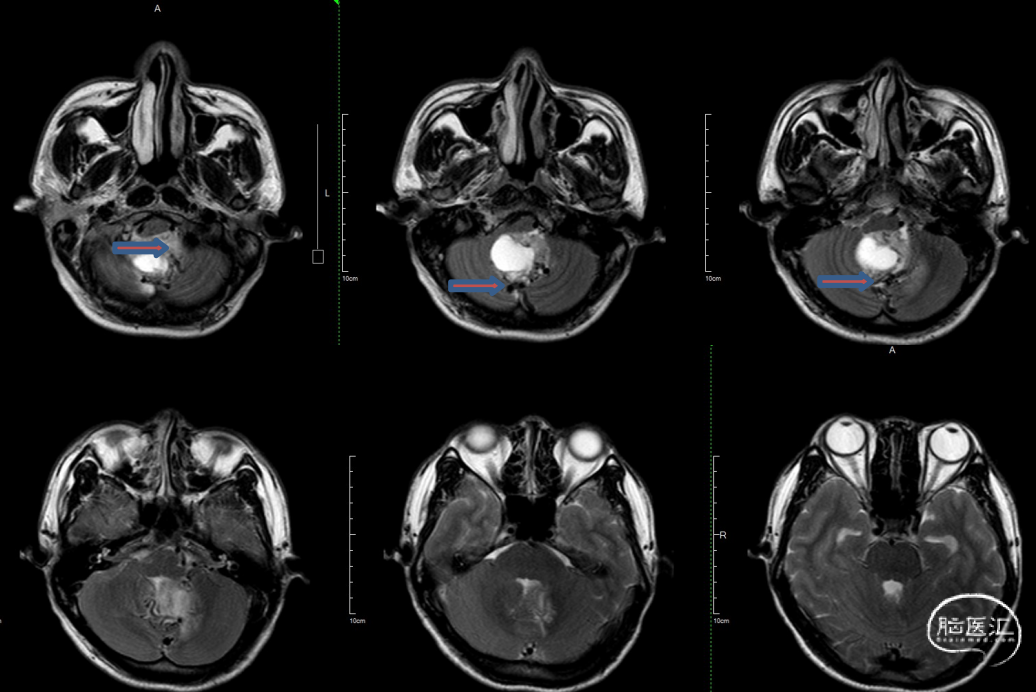

术前MRI:T2显示瘤周大量流空信号影,Flair显示左侧瘤周水肿边界欠清。

T1增强显示肿瘤血供非常丰富,有粗大引流静脉向窦汇及直窦引流。